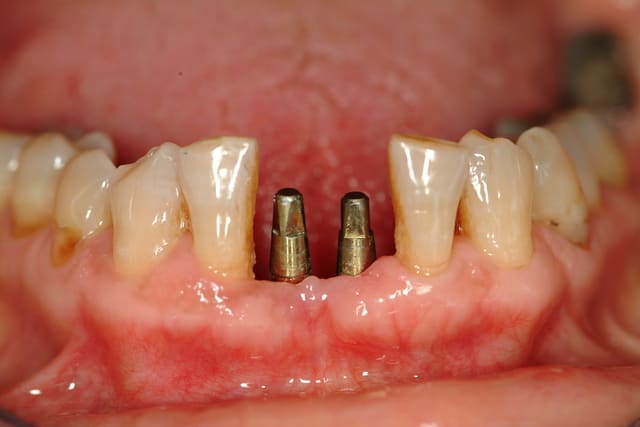

> Cas clinique:

> Edentements de 31 et 41

> Largeur mésio distale : 1.1 cm

> Volume osseux résiduel satisfaisant.

> Occlusion favorable.

A ta place je poserai deux implants Monobloc.

Même les implants de 3.3 mm en deux pièces sont plus volumineux que ces implants Monobloc.

Avantage: ils font 2.9 mm de diam au col et te permettent de garder suffisament d'espace entre les implants et les denst adjacentes.

Inconvénient: comme ils sont Monobloc, le placement doit être idéal, peu de retouches possibles et faire de la mise en temporisation immédiate.

c'est une très bonne solution, d'autant qu'étant monoblocs, il n'existe pas de microgap entre le moignon et l'implant. Ainsi, comme le souligne marcB6, les distances inter-implants et implants-dents peuvent être minimisée: utilisables même en cas d'un espace de 8.7 mm

Bravo, tu as raison, ceux sont des ARRP de chez Alpha bio.

tu doit enfouir la partie sablée de l'implant, elle est grise, le col doré est transmuqueux.

tu peux aussi l'enfouir mais dans ce cas, tu induis une cratérisation et un déplacement apical de ta crête osseuse.

Tu peux effectivement retoucher la partie occlusale, dans une certaine limite, car le moignon est déjà assez fin.

Evdemment, dans ce cas, extraction-implantation et mise en temporisation immédiate.